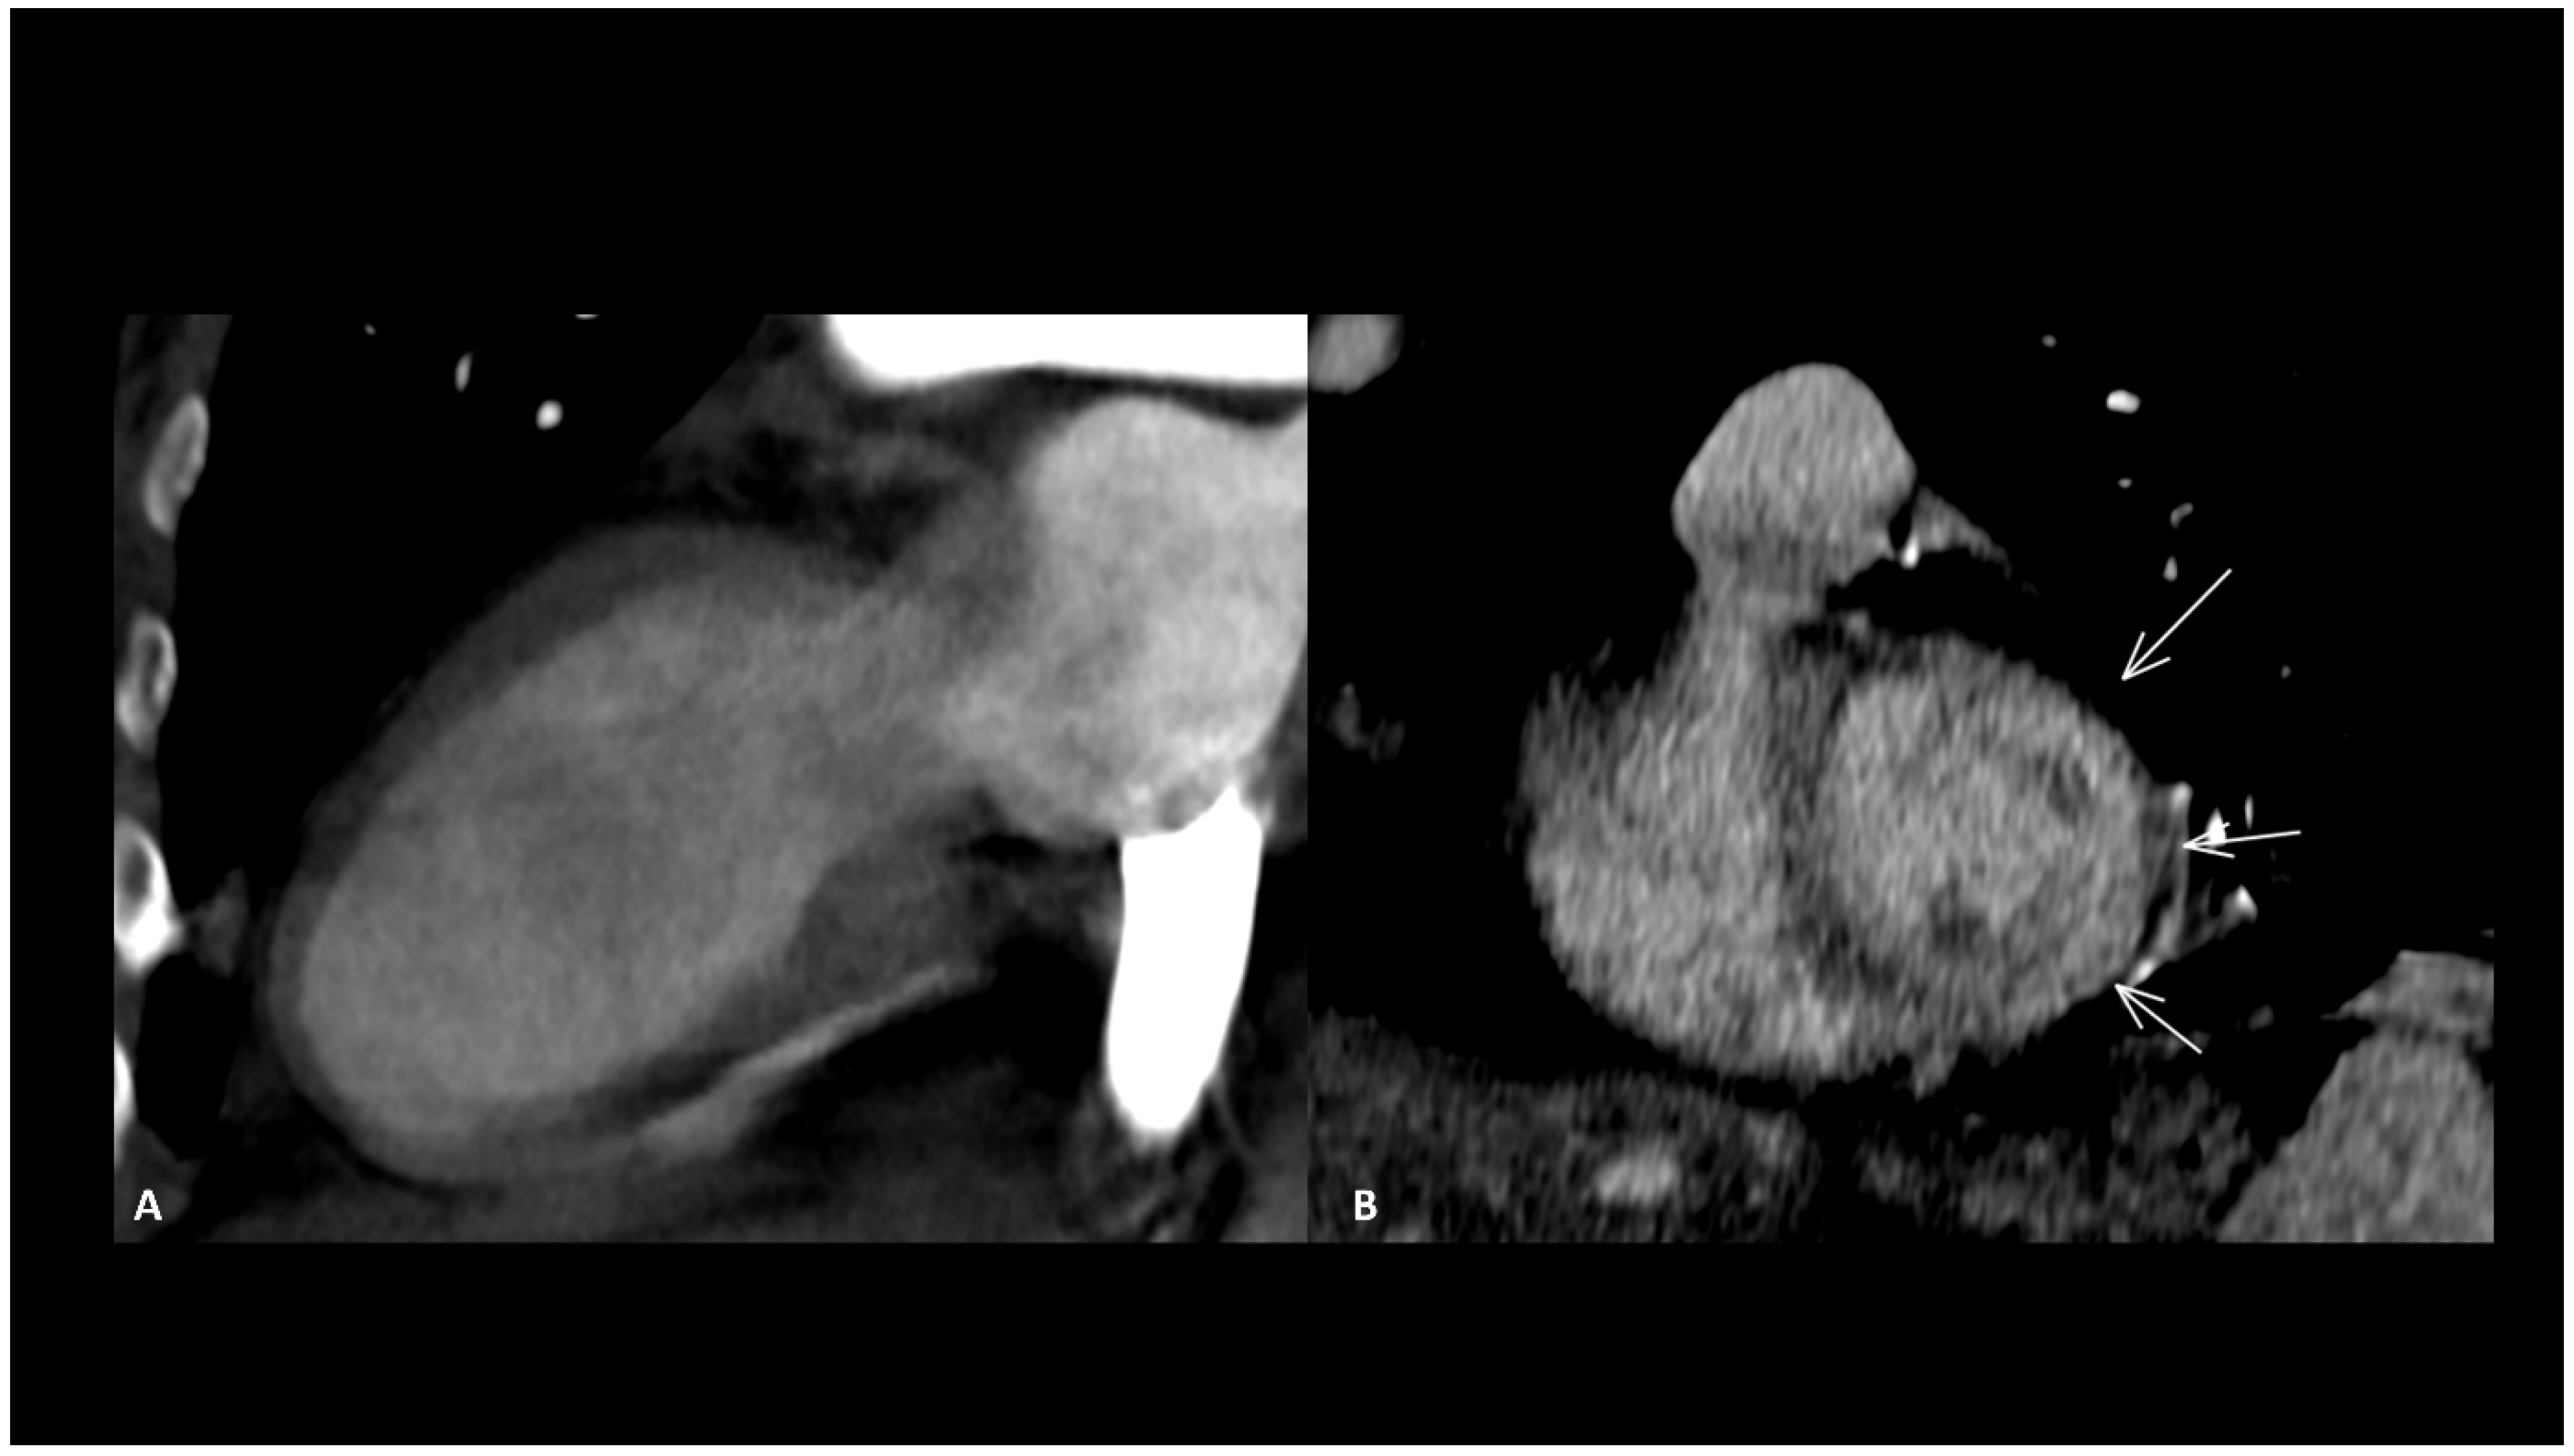

2.3.1. Ir-Myocarditis

- Thavendiranathan, P.; Zhang, L.; Zafar, A.; Drobni, Z.D.; Mahmood, S.S.; Cabral, M.; Awadalla, M.; Nohria, A.; Zlotoff, D.A.; Thuny, F.; et al. Myocardial T1 and T2 Mapping by Magnetic Resonance in Patients with Immune Checkpoint Inhibitor–Associated Myocarditis. J. Am. Coll. Cardiol. 2021, 77, 1503–1516. [Google Scholar] [CrossRef] [PubMed]

- Zhang, L.; Awadalla, M.; Mahmood, S.S.; Nohria, A.; Hassan, M.Z.O.; Thuny, F.; Zlotoff, D.A.; Murphy, S.P.; Stone, J.R.; Golden, D.L.A.; et al. Cardiovascular magnetic resonance in immune checkpoint inhibitor-associated myocarditis. Eur. Heart J. 2020, 41, 1733–1743. [Google Scholar] [CrossRef]

- Cadour, F.; Cautela, J.; Rapacchi, S.; Varoquaux, A.; Habert, P.; Arnaud, F.; Jacquier, A.; Meilhac, A.; Paganelli, F.; Lalevée, N.; et al. Cardiac MRI Features and Prognostic Value in Immune Checkpoint Inhibitor–induced Myocarditis. Radiology 2022, 303, 512–521. [Google Scholar] [CrossRef]